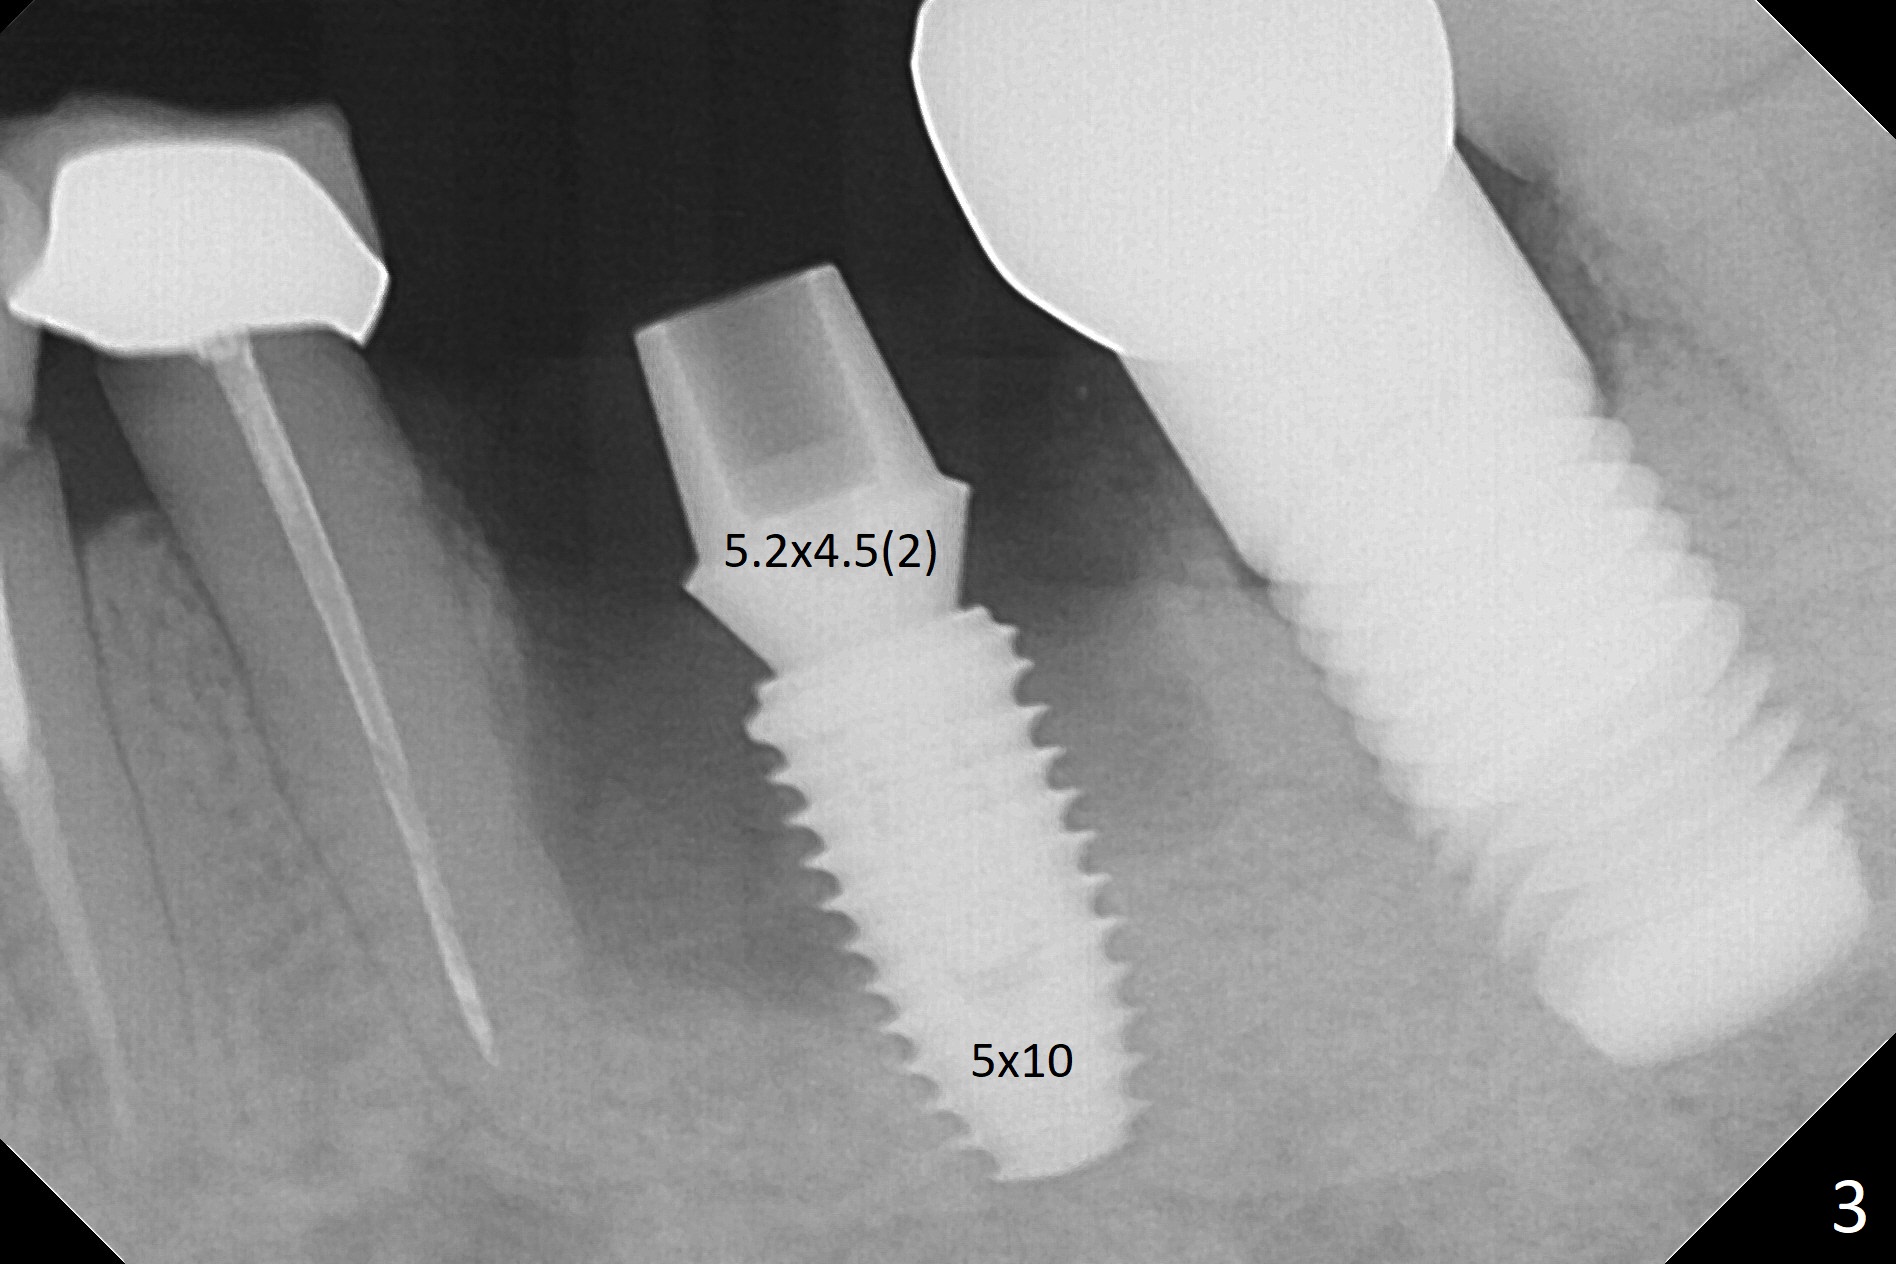

Extraction of the residual roots at #19 (Fig.1) is difficult, partially due to the hard one. The latter contributes to primary stability of 5x10 mm IS implant placed in the septum (Fig.2 (*),3). After change of cementation abutment (5.2x4.5(2) mm (short for provisional)) to hexed temporary abutment (5.2x8(2) mm), Collagen plug and Vera Graft are placed in the remaining mesial and distal socket (Fig.4 *). The last PA is taken when the temporary abutment (Fig.6 (<: hexed portion)) and provisional (P) are removed for modification. Before the abutment/provisional complex returns, a 2nd round of graft is placed (Fig.5 *). After the complex is seated, a 3rd round of graft is placed buccally (Fig.7). The temporary abutment is retightened 2 months postop (Fig.8). The implant appears to be osteointegrated 3.5 months postop (Fig.9). The gingiva looks healthy with (Fig.10) and without the provisional (Fig.11,12). It appears that there is no or minimal buccal plate loss. After insertion of a 5.7 x3 mm 15 degree (B-type) angled abutment (Fig.13) and height adjustment, impression is taken. The provisional is reseated after impression. The mesial bony defect seems to have been repaired nearly 8 months postop, 3 months post cementation (Fig.14 *). The bone density increases mesially 11 months post cementation (Fig.15).